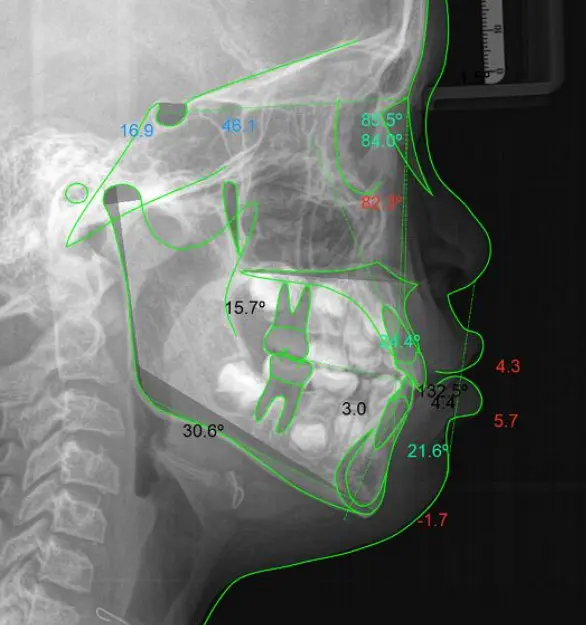

ANÁLISIS CEFALOMÉTRICOS

Es una herramienta clave para evaluar la relación entre los huesos, dientes y tejidos faciales.

ANÁLISIS DE STEINER

Nustros Análisis

- Steiner

- Ricketts

- Tweed

- Arnett

- Mc Namara

- Bjork-Jarabak

- U.S.P

- Downs

- UPCH

- Tejidos Blandos

- INSN

- Otros Análisis a Solicitar